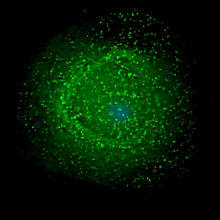

HIV on a macrophage.